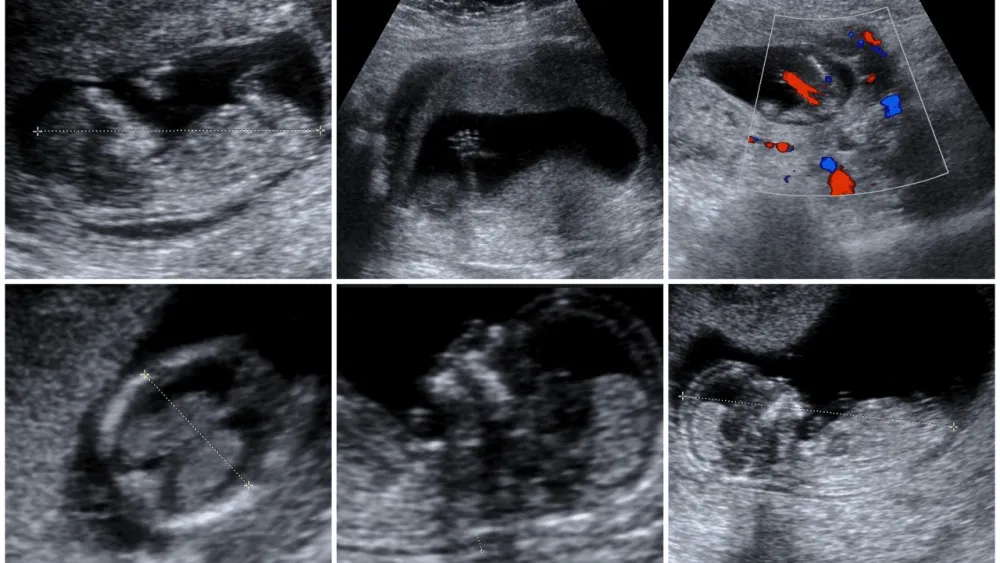

Apa yang dirasakan Ibu jika leher janin terlilit tali pusat? Ibu tidak akan merasakan apa-apa. Namun, sebetulnya kejadian ini dapat dicegah dengan selalu telaten memeriksakan janin melalui ultrasonografi pada waktu hamil tua. Pada ultrasonografi, dokter akan selalu dapat mengetahui kejadian tali pusat yang terlilit dan dapat membahayakan janin, sehingga tindakan untuk mencegah janin mati dapat dikerjakan secepat mungkin.